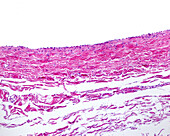

13613516 - Vein adventitia, light micrograph